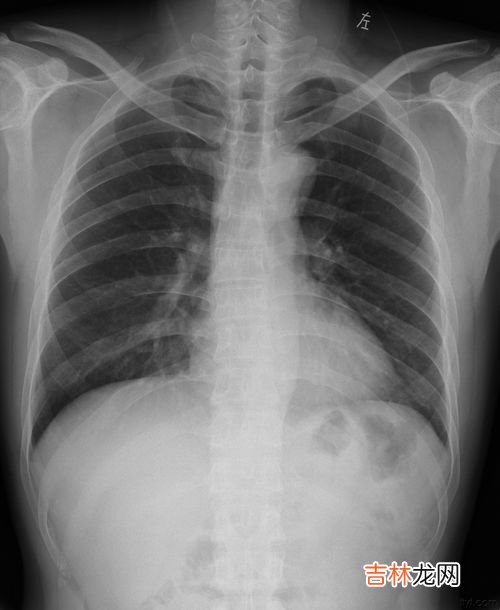

文章插图